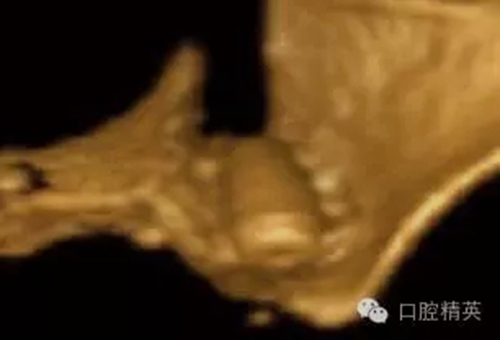

圖7a:6,7號(hào)牙種植體(3*15mm)折斷前,從物理學(xué)理論上講,種植體骨整合后,基臺(tái)螺絲和種植體相連接的支點(diǎn)處是受力時(shí)種植體最薄弱的位置。(a)可見6號(hào)牙種植體的折斷面,和7號(hào)牙種植體上的折裂線(b)

圖7b:6,7號(hào)牙種植體折斷后。

種植體折斷可能發(fā)生于種植體行使功能幾年后,也可能發(fā)生于早期。(圖7a,b)對(duì)于圖中這一病例,治療計(jì)劃是在對(duì)患者的咬合關(guān)系,未來修復(fù)體理化環(huán)境,患者咀嚼習(xí)慣等充分評(píng)估后制定的。種植體折斷后,對(duì)該病例進(jìn)行了回顧性病因分析,上了頜架的模型揭示了過長(zhǎng)的頜間距離,和嚴(yán)重、廣泛的對(duì)頜牙磨耗(圖7c,d)。對(duì)于這一病例,醫(yī)生仔細(xì)評(píng)估了所有可得到的回顧性診斷信息,和患者進(jìn)一步討論交流后,提出了幾個(gè)診斷建議和一個(gè)過渡性治療方案,其中包括將固定修復(fù)改為鑄造可摘局部義齒。

圖7c,d:6,7號(hào)牙的回顧性模型分析顯示為了獲得滿意的美學(xué)效果牙冠不得不做的很長(zhǎng),從而形成較深的咬合關(guān)系。同時(shí)可見對(duì)

頜牙磨耗嚴(yán)重,廣泛。